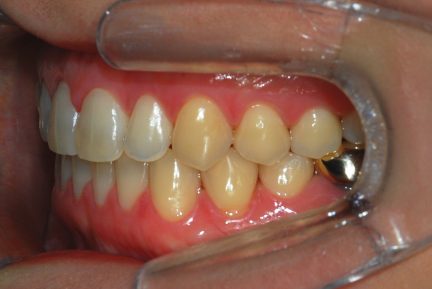

- Articulé postérieur corrigé

- Une surcorrection de l'articulé croisé postérieur a été planifiée pour s'assurer que nous n'aurions pas de contacts prématurés dans la période postopératoire immédiate.

- Entre 3,4 et 3,5, nous n'avons fait qu'une réduction interproximale de 0,3mm pour renforcer la fermeture des espaces.

- La petite déviation médiane a été corrigée avec des aligners supplémentaires.

État final